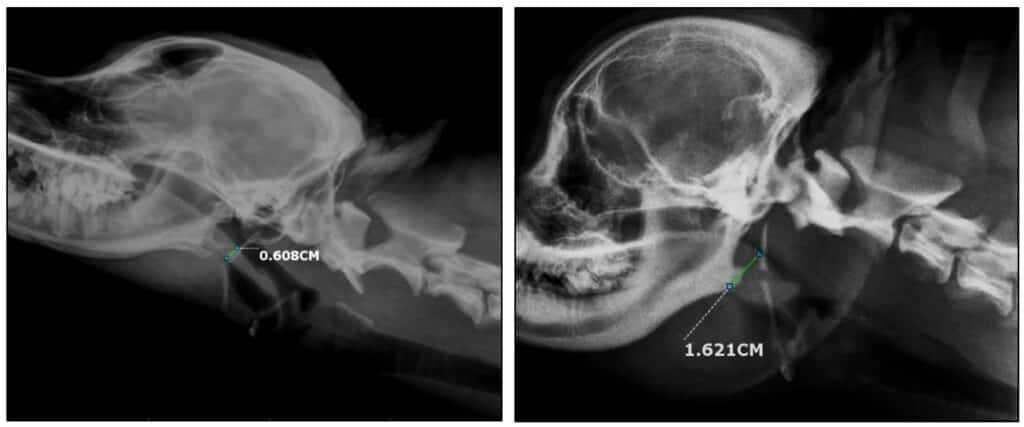

Существует огромный диапазон степени брахицефалии у пораженных ею пород.

Сравните, например, чрезвычайно плоскую морду мопса с небольшим укорочением морды у американского кокер-спаниеля.

Также существуют различия в том, как брахицефалия влияет на разные лицевые кости. У многих брахицефальных пород, таких как мопсы и пекинесы, обе челюсти укорочены.

В то время как у некоторых — например, у боксеров и бульдогов — укороченная верхняя челюсть и нижняя челюсть нормальной длины. Это придает собаке характерно выступающую нижнюю челюсть.

Брахицефалия сопровождается рядом проблем со здоровьем, которые мы рассмотрим сейчас. Но серьезность этих проблем напрямую связана со степенью укорочения черепа.